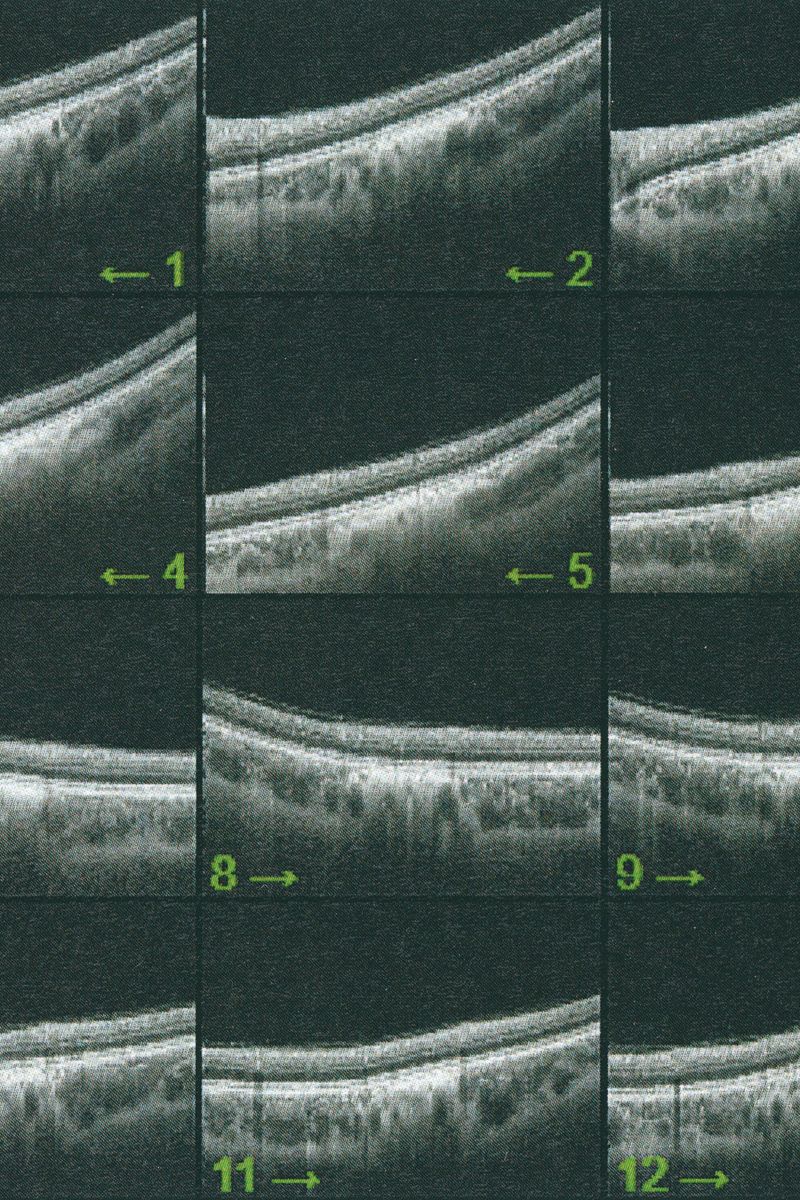

Collirio (Eye wash) is the attempt to demonstrate the non-absoluteness of visual experience, its nature as a situated, and yet, ambiguous act. It is the path that has allowed me to understand how my fears do not have roots in an unknowable place. The eye is not an unfathomable globe.

Collirio is the photographic project I presented for my BA degree at ISIA Urbino. I designed a book (22x29.5cm, 160pages) with text pages and transparent paper inserts and a printed canvas-like dust jacket. A photographic reference scale ruler has been applied on the cover of each of the copies.